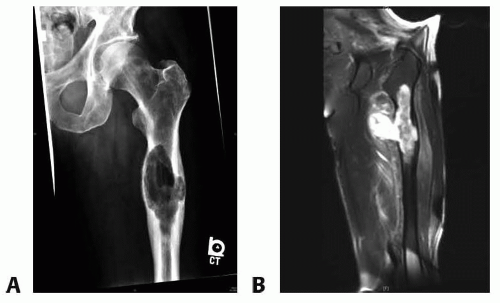

Plain radiographs are used to formulate a differential diagnosis and a preoperative plan (FIG 1A).

Magnetic resonance imaging is routinely used to determine the extent of intramedullary tumor involvement, presence of soft tissue extension, status of the neurovascular structures, and preoperative planning (FIG 1B).

FIG 1 • A. Anteroposterior radiograph of a 67-year-old man with highgrade chondrosarcoma of the proximal femur seen as a large lucent lesion. B. Coronal T2-weighted MRI of the same patient demonstrating extensive soft tissue component and intramedullary involvement by chondrosarcoma.